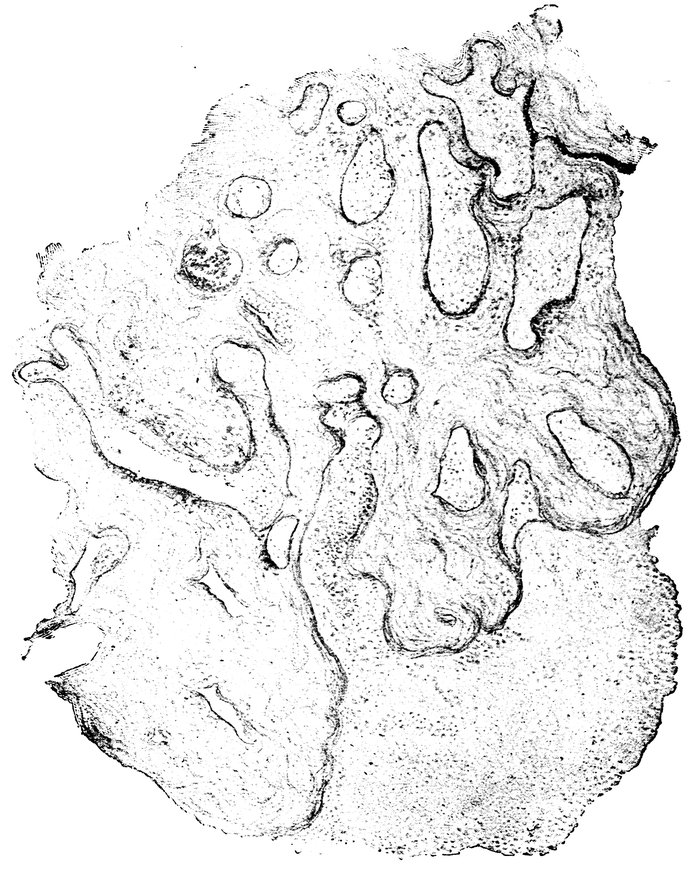

| 52. | Sagittal Section through the Cervix Uteri of a Woman twenty-six years of age. Dendriform branched glands | 217 |

| 53. | Cervix of a Woman seventy-two years of age, with glands that have undergone cystic degeneration | 217 |

| 54. | Sagittal Section through the Cervix Uteri of a Woman sixty-five years of age. The glands have undergone cystic degeneration | 217 |

| 92. | Sagittal Section through the Cervix of a Woman twenty-six years of age. Dendriform branched glands | 588 |

| 93. | Sagittal Section through the Cervix of a Woman sixty-five years of age. Glands which have undergone Cystic Degeneration | 589 |

| 94. | Cervix of a Woman seventy years of age. The Cervical Glands have undergone Cystic Degeneration | 589 |